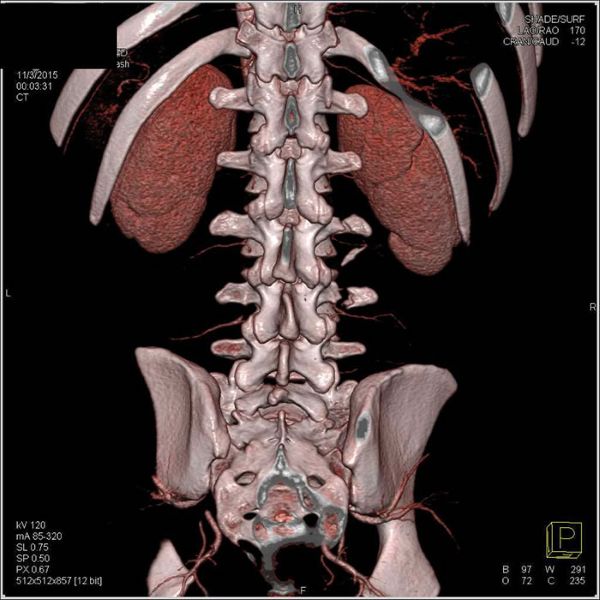

ხერხემლის სვეტის კომპიუტერული ტომოგრაფია (CT)

ხერხემლის სვეტის კომპიუტერულმა ტომოგრაფიამ დღესდღეობით მნიშვნელოვანი ადგილი დაიკავა ხერხემლის სვეტის წელის მალების დაავადებების (კერძოდ კი ოსტეოქონდროზის დროს დისკების თიაქარის) დიაგნოსტიკაში. გამოკვლევის სხვა რენტგენოლოგიურ მეთოდებთან შედარებით ხერხემლის სვეტის კომპიუტერულ ტომოგრაფიას აქვს რამდენიმე უპირატესობა - მეთოდი არაინვაზიურია, თანაც უზრუნველყოფს ძვლოვანი სტრუქტურების, დისკების, იოგების, რბილი ქსოვილების მკვეთრ ვიზუალიზაციას.

ხერხემლის სვეტის კომპიუტერულმა ტომოგრაფია ხერხემლის არხისა და მალთაშუა ხვრელების შემავიწროებელი დისკის თიაქარისა და სხვა ელემენტების პირდაპირი ნიშნების დემონსტრირებას ახდენს, საშუალებას იძლევა განისაზღვროს მათი ადგილმდებარეობა, ზომა და ურთიერთობა ახლომდებარე ანატომიურ სტრუქტურებთან.

ხერხემლის სვეტის კომპიუტერული ტომოგრაფია აჩვენებს მალთაშუა სახსრებისა და მალების სხეულთა დაავადებებისას გამოვლენილ ცვლილებებს.

ხერხემლის სვეტის კომპიუტერული ტომოგრაფიის შედეგების ანალიზის დროს დიდი მნიშვნელობა აქვს მულტიპლანურ რეკონსტრუქციას, რომლის მეშვეობითაც შეიძლება ინტერპრეტაცია მიეცეს არა მარტო მიღებულ აქსიალურ, არამედ საგიტალურ, ფრონტალურ და ირიბ ჭრილებს.